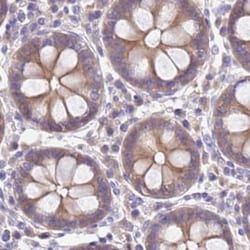

Invitrogen™ STIP1 Polyclonal Antibody

| Immunohistochemistry (Paraffin), Western Blot | |